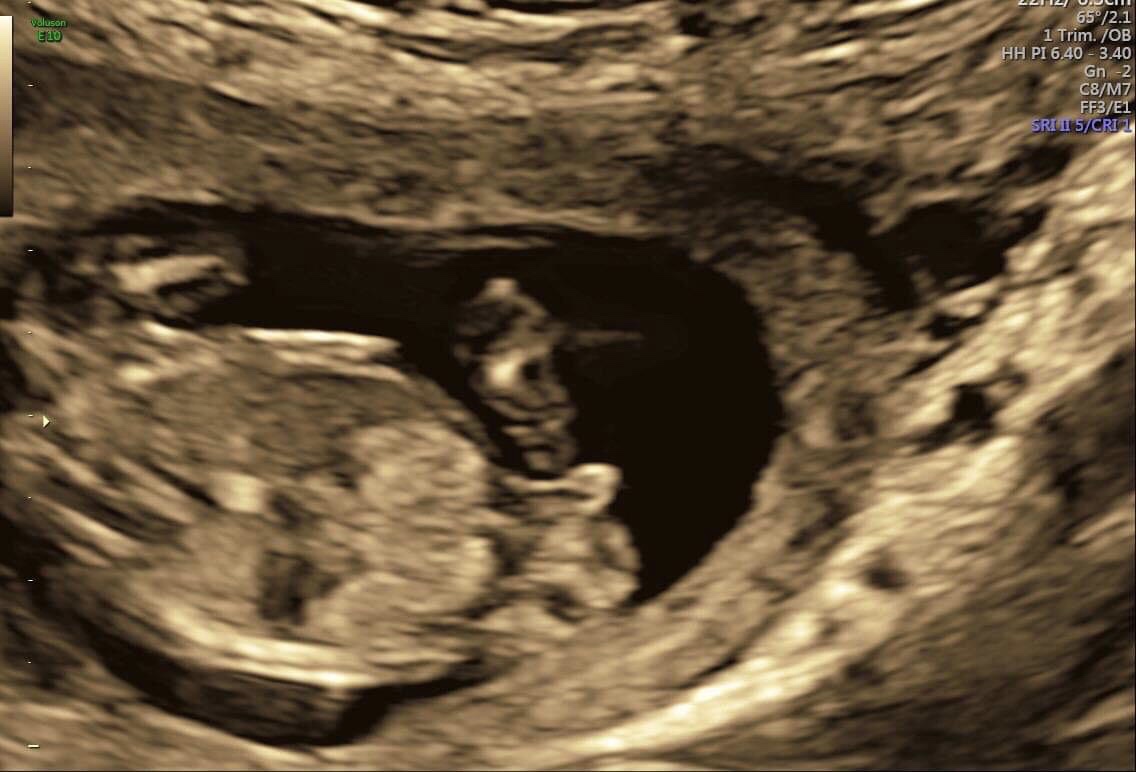

Doctor could not say gender so I made a sono on my own... they are Not quite good, but maybe u can see gender? Pls help me ;-)

The nub seems flat, which is more pink friendly, but the shape and length seem somewhat boyish and makes me wary to sign off on it totally being a girl. Slight pink lean.

The other one started off with the baby facing away, but it turned over midway through. I would give a tentative pink lean (like 52%/48% LOL) but the nub was only visible for a moment, and the baby was in motion when I thought I spotted it, so I don't have much confidence that I can guess accurately. The baby being in motion means that the angle of the dangle is not at all reliable and I just don't like getting anyone's hopes up when I can't give an accurate guess.

There’s absolutely no way you can determine the nub when baby is lying like this. Back needs to be straight.

I have the same problem I had before - I feel like the nub is awfully short for a girl. It's pretty straight, but at the same time it's not that clear cut obvious girl nub. I'm still about 50-50 with a slight pink lean due to what I saw on the video.

these photos which look a bit "orange" (not black/white) are from my 1st trimester screening at a praenatal diagnostic - i hoped he tells me gender, but he didnt... so these are original photos taken at 12+4

the black/white were at 11+?? and the video was at 13+??